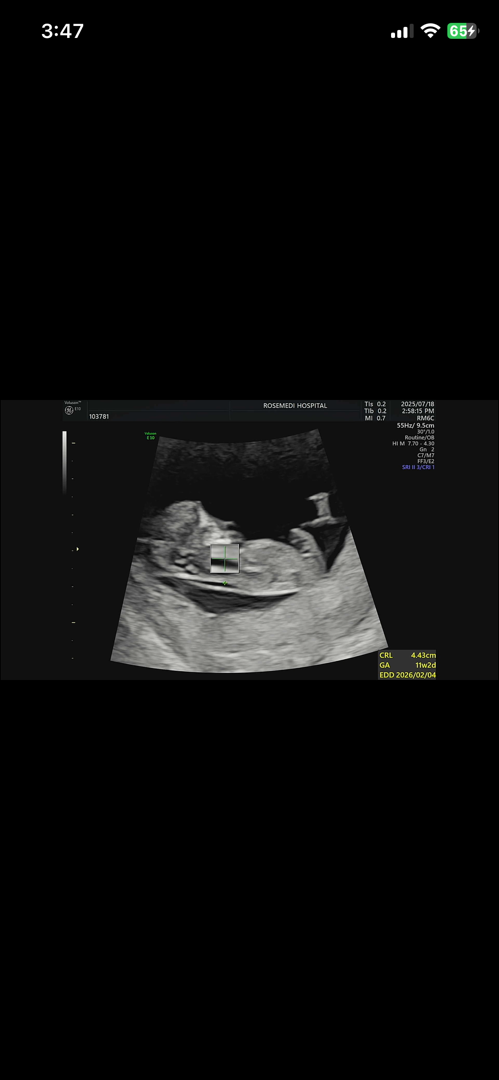

성별 문의드려요 :)

11주인데 성별을 알 수 있을까요? ㅠㅠ

지금봐서는 딸같아욤